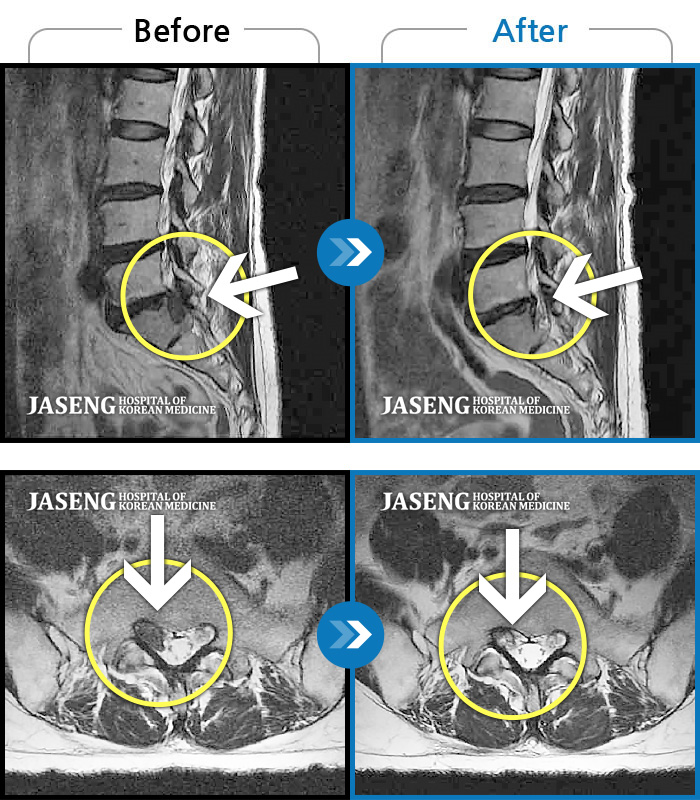

허리디스크

잠실 · 한상욱 원장

허리통증과 함께 좌측 엉치, 허벅지, 종아리 후면으로 저림이 심하여 걷기가 힘들어요.

촬영시기

2021.09.14 ~ 2022.05.14

2022.05.24